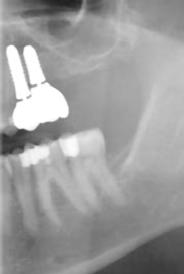

2. a–d ábra: PEEK zárócsavarok az implantátumokba helyezve, 1. eset (a). 2. eset (b). 3. eset (c), 4. eset (d). 3. a–b ábra: Röntgenfelvételek három hónap után (a) és a gyógyulási csavarok behelyezve (b, 1. eset). 4. a–b ábra: Röntgenfelvételek öt hónappal később (a) és a gyógyulási csavarok behelyezve (b, 2. eset). 2. táblázat: Az implantátum tulajdonságai.

5.

Röntgenfelvételek öt hónappal később (a) és a gyógyulási csavarok behelyezve (b és c, 3. eset).

6. a–b ábra: Röntgenfelvételek öt hónappal később (a) és a gyógyulási csavarok behelyezve (b, 4. eset).